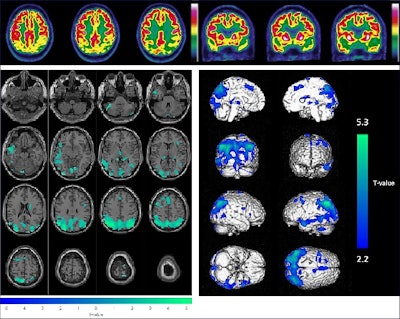

Example of the combined visual (upper panel, axial and coronal slices of brain F-18 FDG-PET images) and semiquantitative (lower panel, with hypometabolisms in green projected on axial MRI slices on the left and hypometabolisms in blue on a 3D volume rendered on the right) analysis for a 65-year-old male patient (initially diagnosed with mild cognitive impairment); these results were consistent with Alzheimer’s disease. The final diagnosis was Alzheimer’s disease and conversion to dementia after 31.5 months.Image and caption courtesy of Alzheimer's Research and Therapy.

According to combined visual and semiquantitative analyses, of the 403 patients, 120 (30%) had normal brain F-18 FDG PET scans; two (< 1%) were abnormal but incompatible with a neurodegenerative disease, and 281 (70%) were classified as neurodegenerative.

Within three years, 105 (26%) patients converted to dementia, and 12 (3%) of these died; 52 (13%) died without any dementia conversion; and 246 (61%) were still alive and did not experience any dementia conversion.

Based on these results, the authors calculated that the F-18 FDG-PET scans had a negative predictive value of 85% for predicting which patients developed dementia.